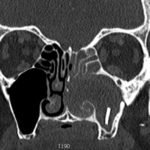

Significant findings:

Computed tomography (CT) sinus with contrast demonstrated complete opacification of left paranasal sinuses and nasal cavity, and a linear radiopacity within the left maxillary sinus consistent with a foreign body. There were additional left facial subcutaneous radiopaque opacities.

In cases of chronic sinusitis that have failed antibiotic therapy, imaging is reasonable to evaluate for underlying etiology.1,2 In one study of 68 patients with unilateral chronic rhinosinusitis who underwent surgery, 11 patients (16%) had an identified object in the maxillary sinus. 10 of these 11 foreign bodies were odontogenic in origin (91%).3 In this case, the patient was prescribed amoxicillin/clavulanic acid, with rapid referral to an otolaryngologist. Subsequent left-sided maxillectomy revealed a piece of irregular brown shiny glass. When asked, the patient had no memory of how this object could have gotten there; given additional subcutaneous hyperdensities noted on CT, trauma is suspected.